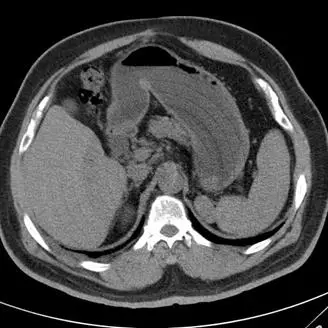

附圖為一張腹部的軸切面(Axial)電腦斷層影像,可以觀察到肝臟、充滿內容物的胃部、脾臟以及脊椎等解剖構造。然而,整個影像上覆蓋了極為明顯、以旋轉中心(Isocenter)為圓心的多圈同心圓環狀圖案(Concentric rings),這些交替的亮暗圓環嚴重干擾了影像品質。這種典型的影像表現在放射線學中稱為環狀假影(Ring artifact)。

- A. 體內有金屬異物:金屬異物(如人工關節、牙骨材或子彈)由於具有極高的原子序和密度,會導致嚴重的射束硬化(Beam hardening)與光子缺乏(Photon starvation),在影像上會呈現以金屬為中心的放射狀條紋假影(Starburst or Streak artifacts),而非同心圓。

- B. 病患不自主移動:病患的呼吸、心跳或不自主移動會導致資料擷取時的空間不一致。這類運動假影(Motion artifacts)在影像上通常表現為解剖構造邊緣的模糊(Blurring)、**重影(Ghosting)**或不規則的條紋,不會形成完美的同